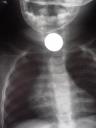

![]()

src=”http://bp1.blogger.com/_I0UHlGxoP6A/Rrzui_RIiAI/AAAAAAAAAAM/_ZAaxAkLSFQ/s320/Clip.jpg”

border=”0″ alt=””id=”BLOGGER_PHOTO_ID_5097211163142817794″ />